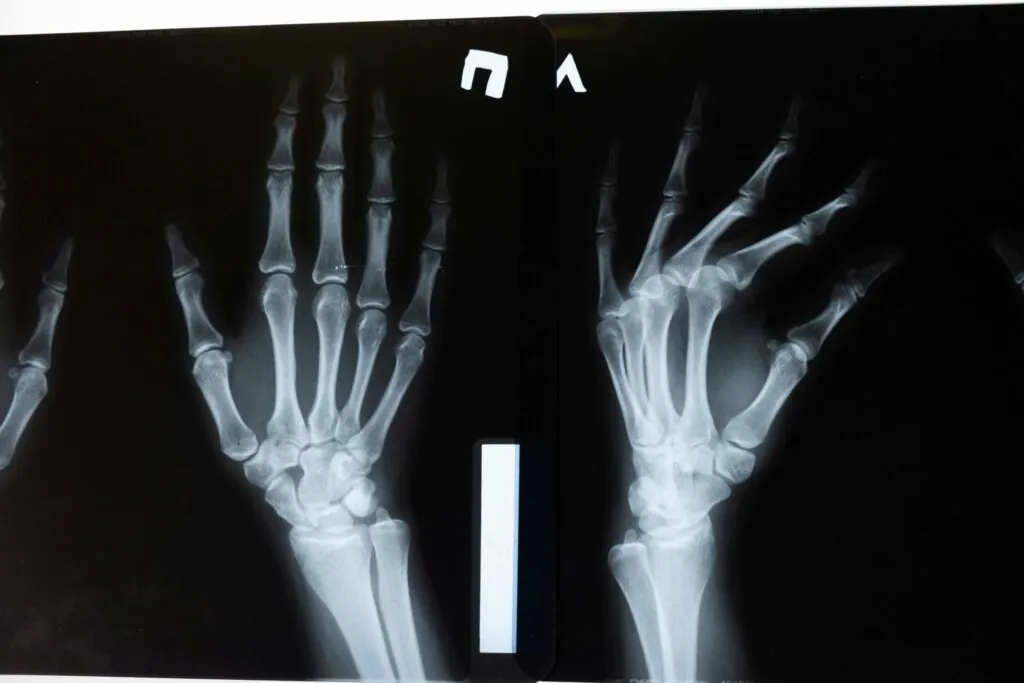

Medical Travel is the rapidly-growing practice of travelling across international borders to seek best healthcare services.

Patients travel abroad for medical care because of affordability and better access to a higher or more specialized quality of care.